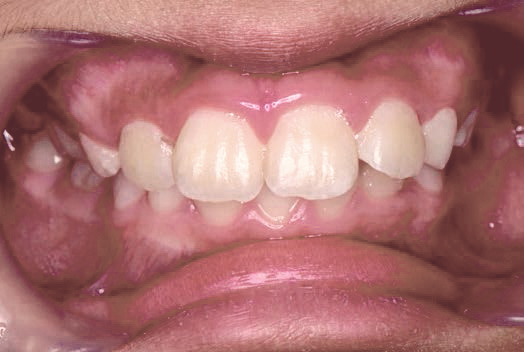

でこぼこ

現役歯科医師の愛娘さんの治療

Nさん (矯正開始時:8歳)

Before

After

上あごの成長が少なく、特に前歯のガタガタが目立っていました。口呼吸のクセや飲み込み方に良くないクセが確認されました。

治療を終えて

マイオブレイスとBB1装置で上あごの成長を助け、鼻呼吸や正しい飲み込み方を身につけることで、きれいな歯並びとしっかり噛めるお口に変わっていきました。

姿勢やお口の機能を正しく整えたので、後戻りしない綺麗な歯並びを維持できています。もちろん非抜歯です。

主訴・治療内容 当院と交流のある歯科医師の先生が、ご自身のお子さまの治療を任せてくださいました。

「難しい歯並びでも永久歯を抜かず、全身の健康と顔立ちも考えて治療してくれる」と信頼していただいて治療開始。

治療期間 3年

費用 462,000円(税込)